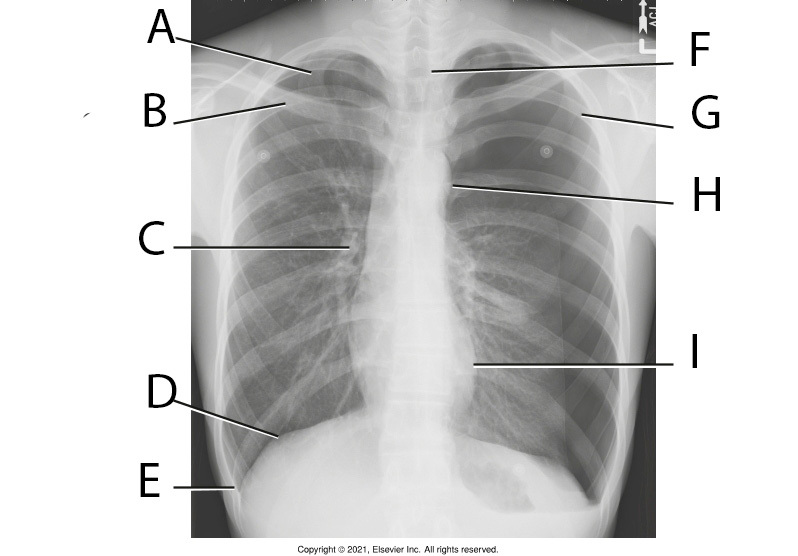

10

Q

A

Apicies

11

B

Thoracic Vertabrae

12

C

Posterior Ribs

13

D

Costrophrenic Angle

14

E

Body of Sternum

15

F

Heart

16

G